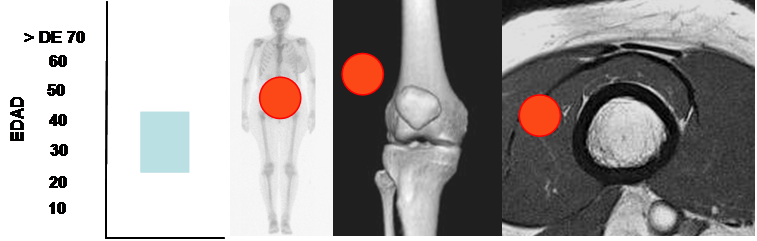

Tumor desmoide:

Se identifica en adultos jóvenes y por fuera de la cavidad peritoneal. Los músculos recto

anterior y oblicuo interno, son los mas comúnmente comprometidos. (28). (Fig 116).

Son lesiones intramusculares de señal variable, heterogénea y generalmente isointensa al músculo en T1 e intermedia en T2. (28). (Fig 117 y 118).

Su recurrencia local después del tratamiento es alta. (28).

Fig 116. Tumor desmoide.

Mayor frecuencia en adultos jóvenes. Predominio en los músculos de la pared abdominal.